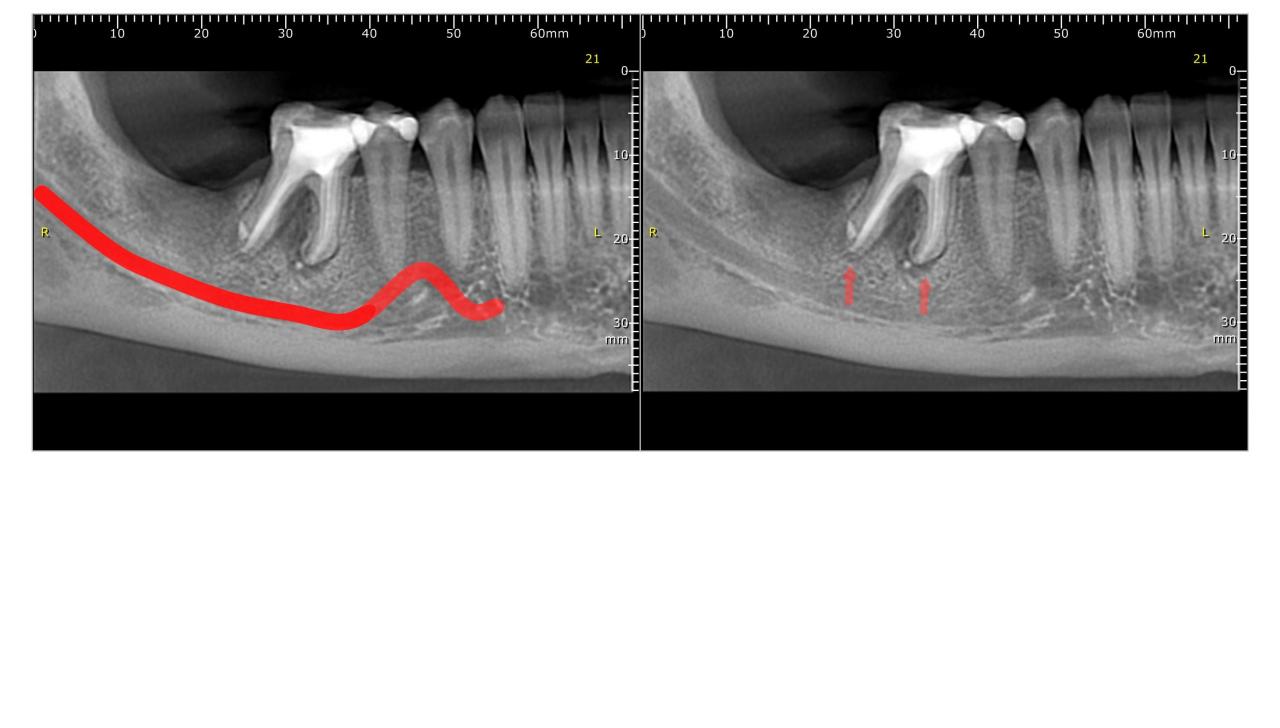

Добрый день. Ищу экспертное мнение. Кто может посмотреть КТ и сказать шо там как. А то я запуталась

Показать скрытый текст

тык

Цитата Сообщение от Zara20 Посмотреть сообщение

Здравствуйте.

Места под имплантант маловато, разве что, на маленький 8 мм

Шестерка с воспалительным процессом. Только вопрос в том, когда она лечилась... Если до 1-3 мес. назад, то можно еще понаблюдать за "восстановлением", если же - 1 год и позже, тогда все очень печально...

Цитата Сообщение от eugtar Посмотреть сообщение

Спасибо за ответ. 6ку давно лечили. Я хотела удаление двух зубов и импланты. Подскажите пожалуйста как сейчас правильно поступить. На 7ку можно "нарастить" кость? А 6 тогда удалять и потом два импланта сразу ставить? Или как правильно?

Если правильно, то нужно смотреть в кресле)

Теоретически 6-ку можно удалять не всю, а только проблемный корень, а дальше – есть варианты восстановления. Но опять же – нужно видеть…

С наращиванием кости уже сложнее, но если задаться целью и при наличии финансов, то можно пробовать что угодно…

а вообще ищу кто посмотрит, проконсультирует, посчитает

уже столько раз меня обманывали

посоветуйте пожалуйста